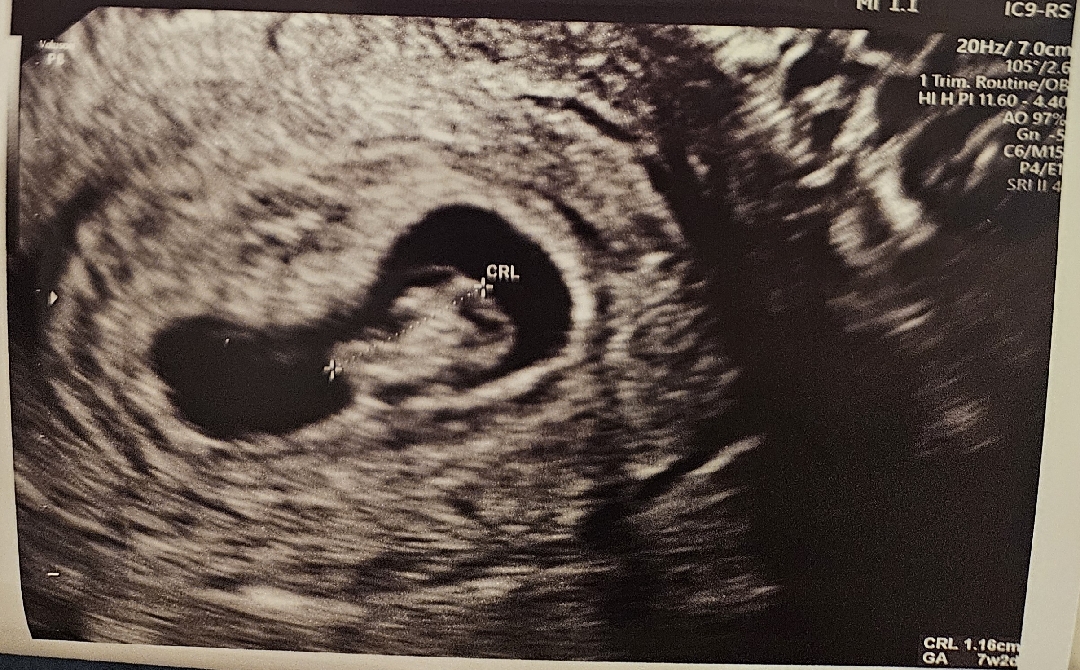

7주2일차 아기집이 작대요..

아기는 주수에 맞게 잘 크고있는데 아기집이 6주4일정도의 크기라고 하시네요.. 다음주에 다시 보자고하셨지만 괜히 불안해요ㅠㅠ 아기집이 많이 작은건가요..?저처럼 초반에 작았는데 괜찮아지신분 계신가요..